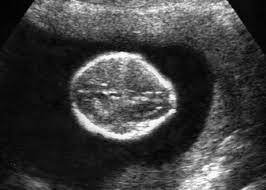

A Review On Techniques For Computer Aided Diagnosis Of Soft Markers For Detection Of Down Syndrome In Ultrasound Fetal Images Biomedical And Pharmacology Journal